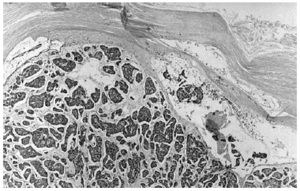

Se realizó una biopsia amplia de la lesión, incluyendo la tumoración nodular. En el examen histopatológico se podía observar una epidermis eosinófila, con una desestructuración que afectaba todo su espesor, ocupada en todo su grosor por queratinocitos atípi-cos con frecuentes mitosis, la mayoría de ellas atípicas. En el estrato córneo había hiperqueratosis, con áreas de paraqueratosis. En dermis superficial existía un infiltrado inflamatorio crónico en banda formado predominantemente por linfocitos con algún histiocito aislado (fig. 2).

Fig. 2.--Alteración de todo el espesor de la epidermis circundante, con paraqueratosis, células disqueratósicas y mitosis.